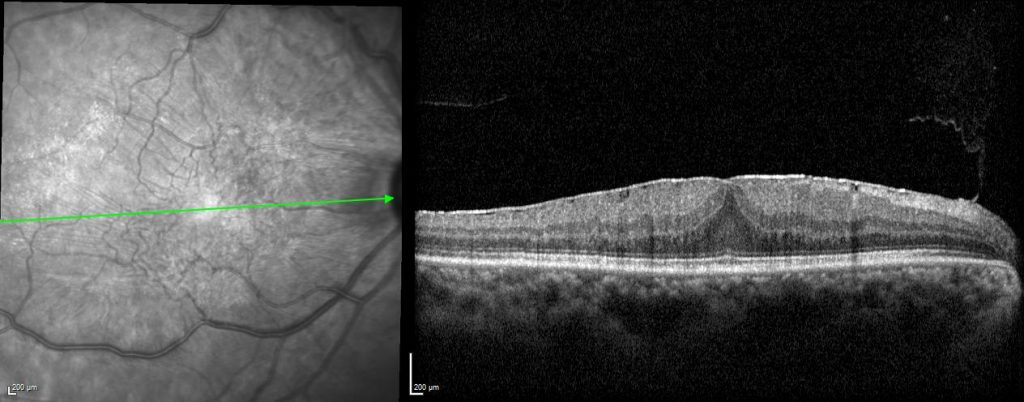

An epiretinal membrane is a thin layer of tissue that has formed on the retina. This then causes wrinkling of the retina. If this tissue is over the macula, it can lead to blurred and distorted central vision.

Epiretinal membranes typically form after a posterior vitreous detachment (PVD). A PVD occurs when the vitreous pulls away from the retina. The vitreous is a jelly-like substance in the eye that helps it maintain a round shape. This happens during the natural ageing process, but can also occur after surgery or inflammation of the eye.